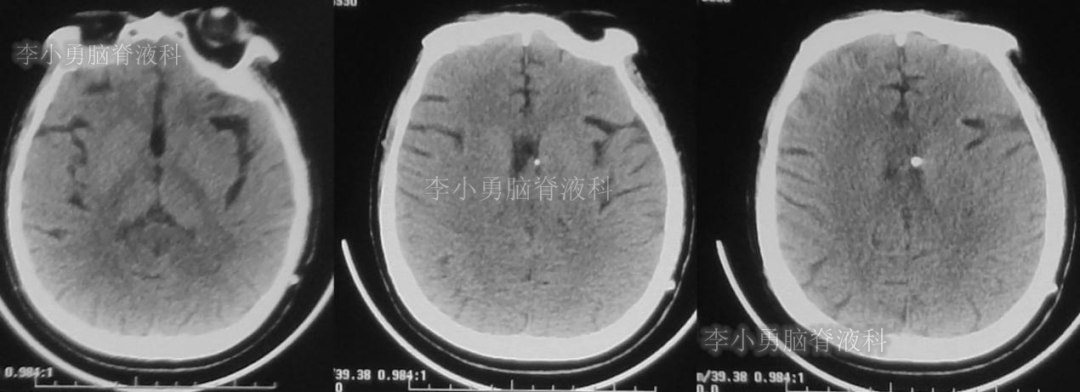

患者于2018年1月29日,突发头痛、头晕、恶心、呕吐,并高热40度。在当地医院门诊输入4天抗生素后发热缓解,但出现了双眼不能上视(眼球不能向上看)。5天后即2018年2月3日,在当地的第1家医院:浙江省海宁市某医院行头颅CT(图-1)发现脑室扩张,当地医院诊断为“梗阻性脑积水”。

图-1:2018年2月3日头颅CT